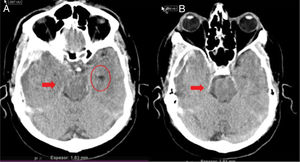

En la práctica clínica, antes de establecer un pronóstico definitivo, se recomienda la opinión de un equipo multidisciplinar experto, que minimice el sesgo personal; en esta valoración el especialista en Medicina Intensiva, por sus conocimientos sobre la enfermedad neurocrítica, juega un papel primordial. La lesión cerebral catastrófica condiciona una elevada presión intracraneal (PIC), con una disminución de la presión de perfusión cerebral e instauración progresiva de la parada circulatoria cerebral. La probabilidad de evolucionar a ME ha de sustentarse en datos clínicos, de neuromonitorización y resultados de la tomografía computarizada (TC) craneal. En primer lugar, hay que tener en cuenta la situación clínica neurológica, medida por las escalas habituales de gravedad según las diferentes enfermedades (escalas de Glasgow [GCS], Hunt y Hess, NIHSS), así como la ausencia de algunos reflejos de tronco del encéfalo. Las escalas de gravedad realizadas en las primeras horas de la lesión tienen sus limitaciones y su valor pronóstico mejora cuando se realizan después de la reanimación del paciente. La probabilidad de error pronóstico es siempre menor cuando estas escalas tienen un valor extremo; a mayor gravedad clínica, mayor probabilidad de evolución a ME37. En este sentido, algunos estudios encuentran que la abolición de 3 reflejos de tronco al ingreso es la variable que más predice la evolución a ME38. Otro de los factores pronósticos que pueden ayudar a predecir una alta probabilidad de evolución a ME es la TC craneal, ya que permite documentar el tipo, el volumen, la localización y la gravedad de la lesión estructural, así como la existencia de signos de hipertensión intracraneal y herniación cerebral. En las hemorragias cerebrales, el volumen del hematoma es uno de los predictores más potentes de evolución a ME y algunos autores encuentran que un volumen superior a 65cc es un factor determinante39. Igualmente, la presencia del «signo del remolino» en la TC sin contraste y del spot sign en la angio-TC nos indica que hay presencia de sangrado activo por arteriolas o vénulas y es un signo de mal pronóstico que algunos autores asocian con una mayor probabilidad de evolución a ME38,40,41. El desplazamiento de la línea media nos informa del grado de compresión y es un indicador, junto con el estado de las cisternas de la base, del compromiso de las estructuras encefálicas. El borramiento parcial o total de las cisternas de la base es un fuerte indicador de probable evolución a ME42. La presencia de signos de herniación cerebral en la TC implica hipertensión intracraneal y, por lo tanto, riesgo elevado de enclavamiento cerebral. Los 3 tipos más frecuentes de herniación cerebral son: herniación subfalcial, que se caracteriza por un desplazamiento de la línea media y compresión del ventrículo lateral ipsilateral (fig. 1), la herniación uncal o transtentorial, donde existe una dilatación de la cisterna del ángulo pontocerebeloso ipsilateral y del cuerno temporal del ventrículo lateral contralateral (fig. 2), y la herniación amigdalina, que se caracteriza por la desaparición de la cisterna magna y el descenso de las amígdalas cerebelosas por debajo de la línea de Chamberlain. La vaina del nervio óptico se continúa con las meninges del sistema nervioso central y acumula líquido cefalorraquídeo en este espacio subaracnoideo, aumentando su diámetro cuando hay un incremento de la PIC. Su diámetro se puede medir por ultrasonidos, resonancia magnética y TC craneal, y aunque no existe unanimidad sobre el lugar de la medición ni el diámetro necesario para considerar hipertensión intracraneal, algunos autores confirman que un diámetro de la vaina del nervio óptico>5-6mm tiene una fuerte correlación con una PIC superior a 20mmHg43,44.

Herniación uncal o transtentorial. A: colapso del asta temporal y de la cisterna ambiens ipsilateral a la lesión expansiva (flecha). Dilatación del asta temporal contralateral (círculo). B: dilatación de la cisterna cerebelopontina ipsilateral (flecha). (Cortesía de Ángela Meilán, Servicio de Radiología del Hospital Universitario Central de Asturias).